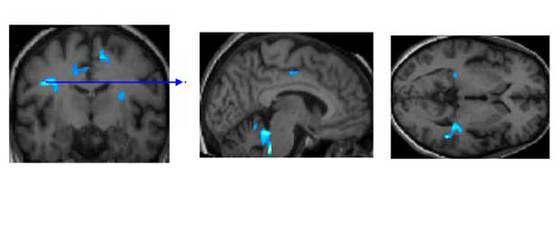

Cerebro de una persona mayor de 65 años sana

Mueve tus neuronas, rejuvenecerás